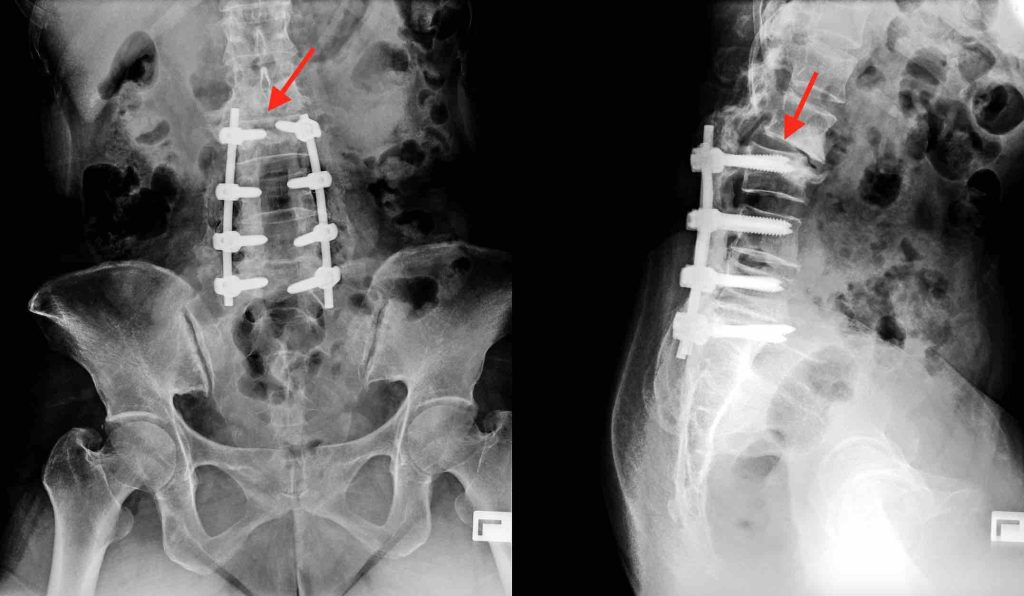

Imagen de radiografía que ilustra el SSA o SNA en la columna vertebral

La artrodesis vertebral fusiona segmentos de la columna vertebral, lo que significa que las vértebras adyacentes tienen que soportar más carga de trabajo. Con el tiempo, este estrés adicional puede provocar cambios degenerativos en la articulación adyacente, lo que se conoce como síndrome del nivel adyacente (SNA) o del segmento adyacente (SSA).

El SNA/SSA se produce en la vértebra adyacente a la artrodesis, ya sea por encima o por debajo de ella. Esta afección puede incluir una combinación de cambios degenerativos, inestabilidad, compresión nerviosa e incluso hernia discal. Los estudios indican que la incidencia de SNA/SSA después de una artrodesis de dos o mas vértebras varía del 25 al 40% después de 10 años.